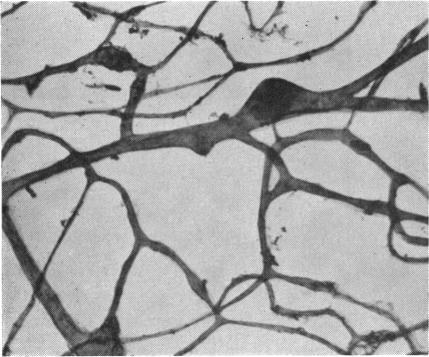

RETINAL PATHOLOGY AFTER CENTRAL RETINAL VEIN OCCLUSION.

Br J Ophthalmol. 1961 Oct;45(10):683-94. doi: 10.1136/bjo.45.10.683.